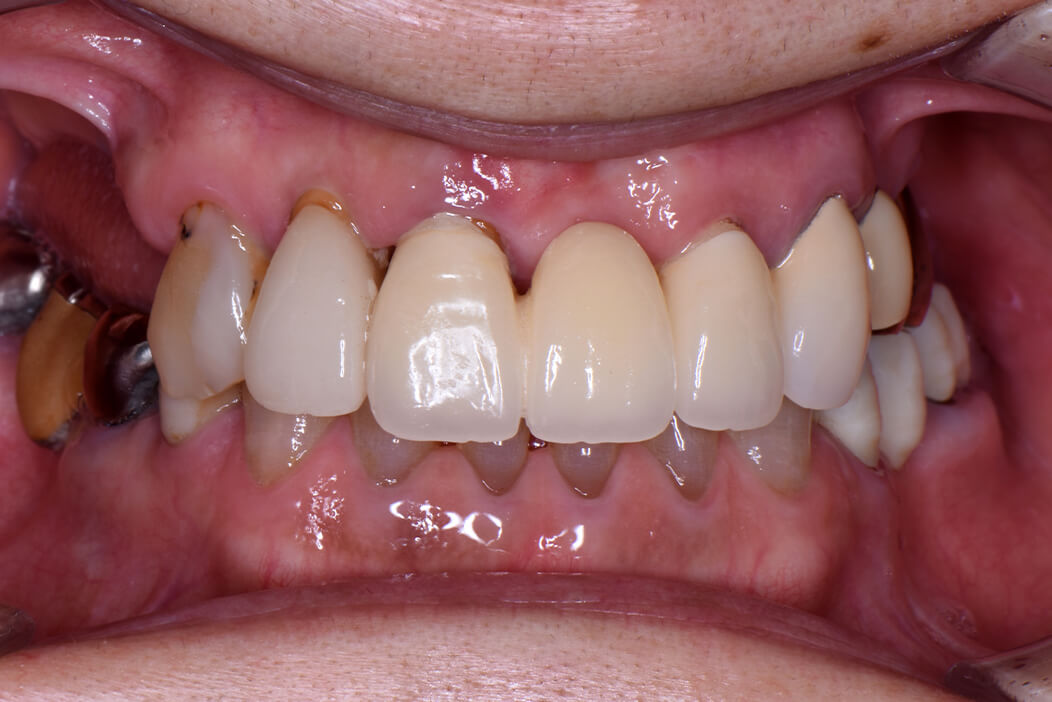

女性/60代

費用/4,527,600円(内矯正治療356,400円)

治療期間/1年5ヶ月

治療内容の詳細/

治療が苦手だが頑張って全体的に治したいと歯科治療を希望。

術前のX線、CT撮影により保存が可能な歯、不可能な歯を選別し、患者様が出来るだけ歯を残したいという希望も考慮して治療計画を立てました。

先ずは保存不可能な歯を抜歯して、臼歯部にストローマン社製ティッシュレベルインプラント、BLTインプラントを埋入し、約2ヶ月後に仮歯を入れて奥歯の噛む位置を決定し、下顎の前歯の叢生(デコボコ状態)はマウスピース矯正(クリアコレクト)を使用して歯列矯正を行い、その後上顎の前歯の欠損部にはストローマン社製BLTインプラントを埋入し、約2ヶ月後に仮歯を入れました。全体的に仮歯の状態で噛み合わせの調整をした後、口腔内スキャナーでデジタル印象を行い、自身の歯にはジルコニアセラミッククラウン、インプラント部にはスクリュー固定式のジルコニアセラミッククラウンを作成し装着しました。約1年5ヶ月の治療期間でしたが、患者様は最後まで頑張って治療を受けていただきました。